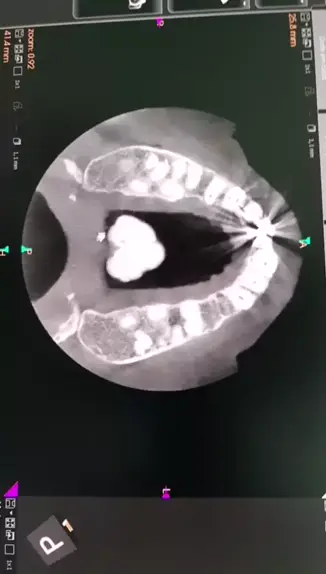

Tc.maxila Torus Más